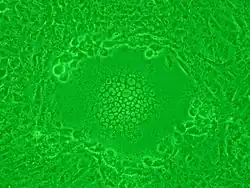

Syncytium vzniklé napadením buněk virem HIV

Syncytium (soubuní) je mnohojaderný buněčný útvar, který vznikne rozrušením buněčných membrán několika sousedních buněk a dojde ke splynutí jejich cytoplazem. Ve výsledku se tedy jedná o buňku obsahující více jader.

Syncitiální buňky jsou například svalová vlákna (myocyty v příčně pruhované svalovině). Vznik syncytií však může v lidském těle způsobit i virové onemocnění, například virus HIV, známé jsou tím i paramyxoviry.